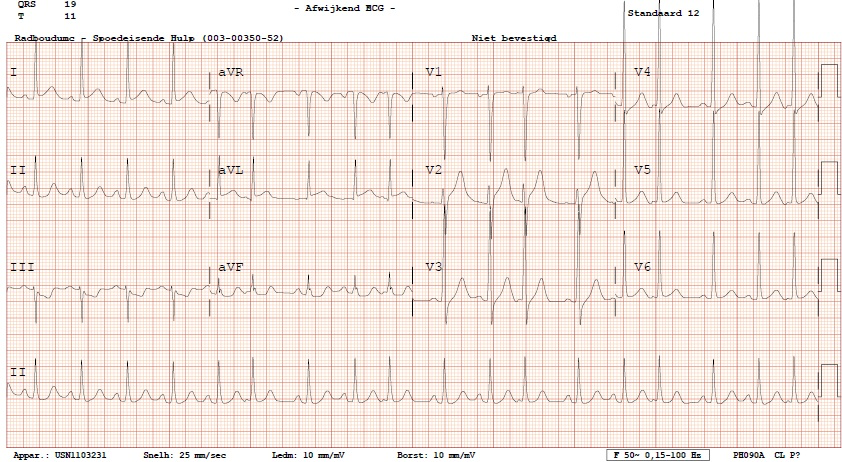

Figuur 2 – Elektrocardiogram bij aankomst

Sinusritme, intermediaire hartas, geleidingstijden binnen de norm. ST-segment elevaties in afleidingen I en aVL met reciproke depressie in III en aVF. Positieve criteria voor linkerventrikelhypertrofie.